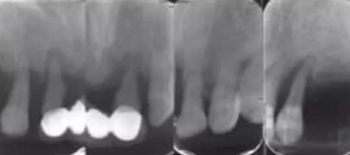

影像學檢查:下頜修復體與種植體邊緣密合,種植體周圍并無明顯異常,14、13、21、22、24、25見根尖陰影,牙槽骨吸收至根尖1/3。23見牙周膜增寬影,牙槽骨吸收至根中1/2(圖2,3)。診斷:上頜牙列缺損(15、16、17、26、27缺失);上頜廣泛性重度牙周炎;14、13、21、22、25根尖周炎。

圖2 術前根尖片檢查